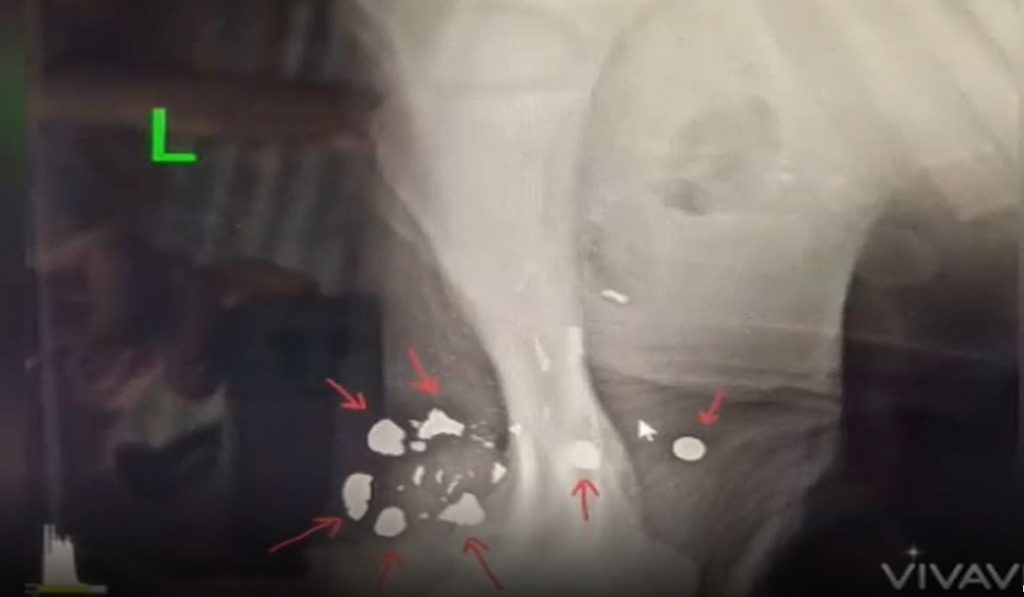

ส่วนบาดแผล ที่มีลักษณะเป็นรูถึง 8 แห่ง บริเวณต้นขาหน้าข้างซ้าย จากผลเอกซเรย์ พบมีหัวโลหะและเศษโลหะ คาดว่าเป็นกระสุนอาวุธปืนไม่ทราบชนิด ฝังอยู่ในกล้ามเนื้อ ลึกมาก จึงไม่สามารถนำออกมาได้ ซึ่งวิธีการผ่านำออกมาจำ เป็นต้องวางยาเพื่อดำเนินการผ่าตัดตามขั้นตอน อาจจะทำให้มีภาวะมีความเสี่ยง และทำให้เสียเลือดมาก เนื่องจากลูกช้างยังมีสภาพไม่สมบูรณ์แข็งแรงพอ เบื้องต้นจึงล้างแผล และใส่ยาฆ่าเชื้อเฉพาะที่ พร้อมปิดแผลป้องกันสิ่งสกปรกและแมลง